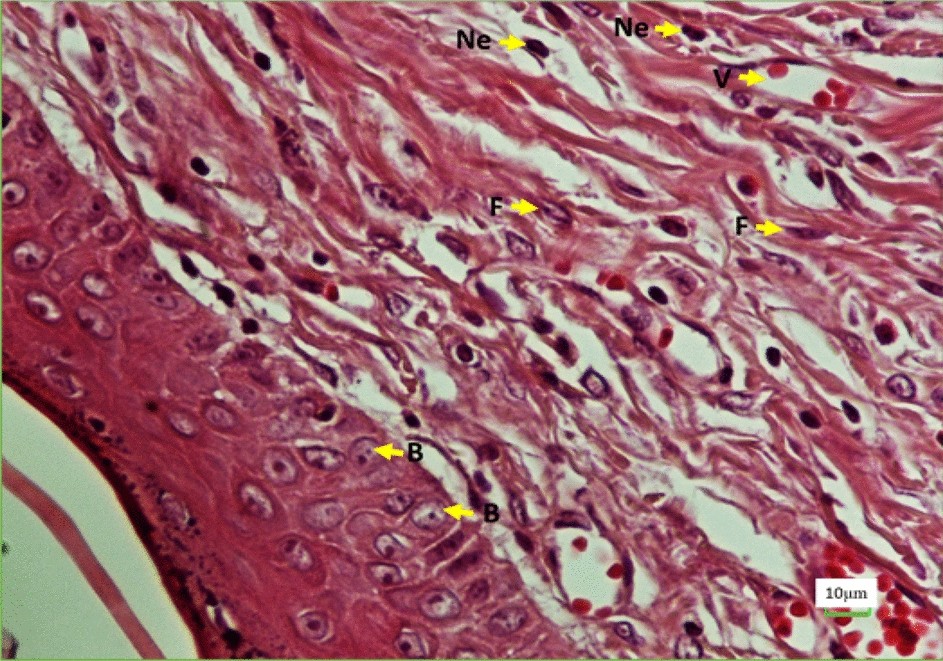

Photomicrograph of the wound healing area following injury stained with H&E (×40). Ne neutrophils, F fibroblasts, B basal cells, V vessel.